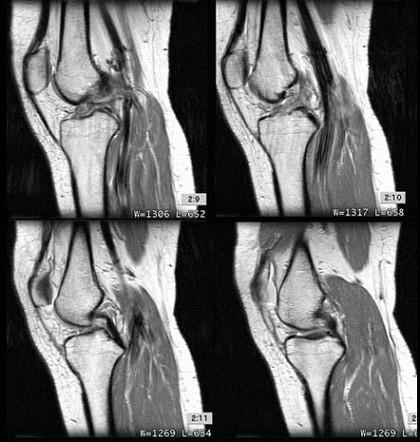

问题 男,37岁,右膝关节曾有外伤史,现感右膝关节部疼痛,请结合所提供的图像,选择最佳选项 ( )

选项 A、半月板损伤 B、后十字韧带撕裂 C、前十字韧带撕裂 D、胫骨骨折 E、未见异常

答案 C